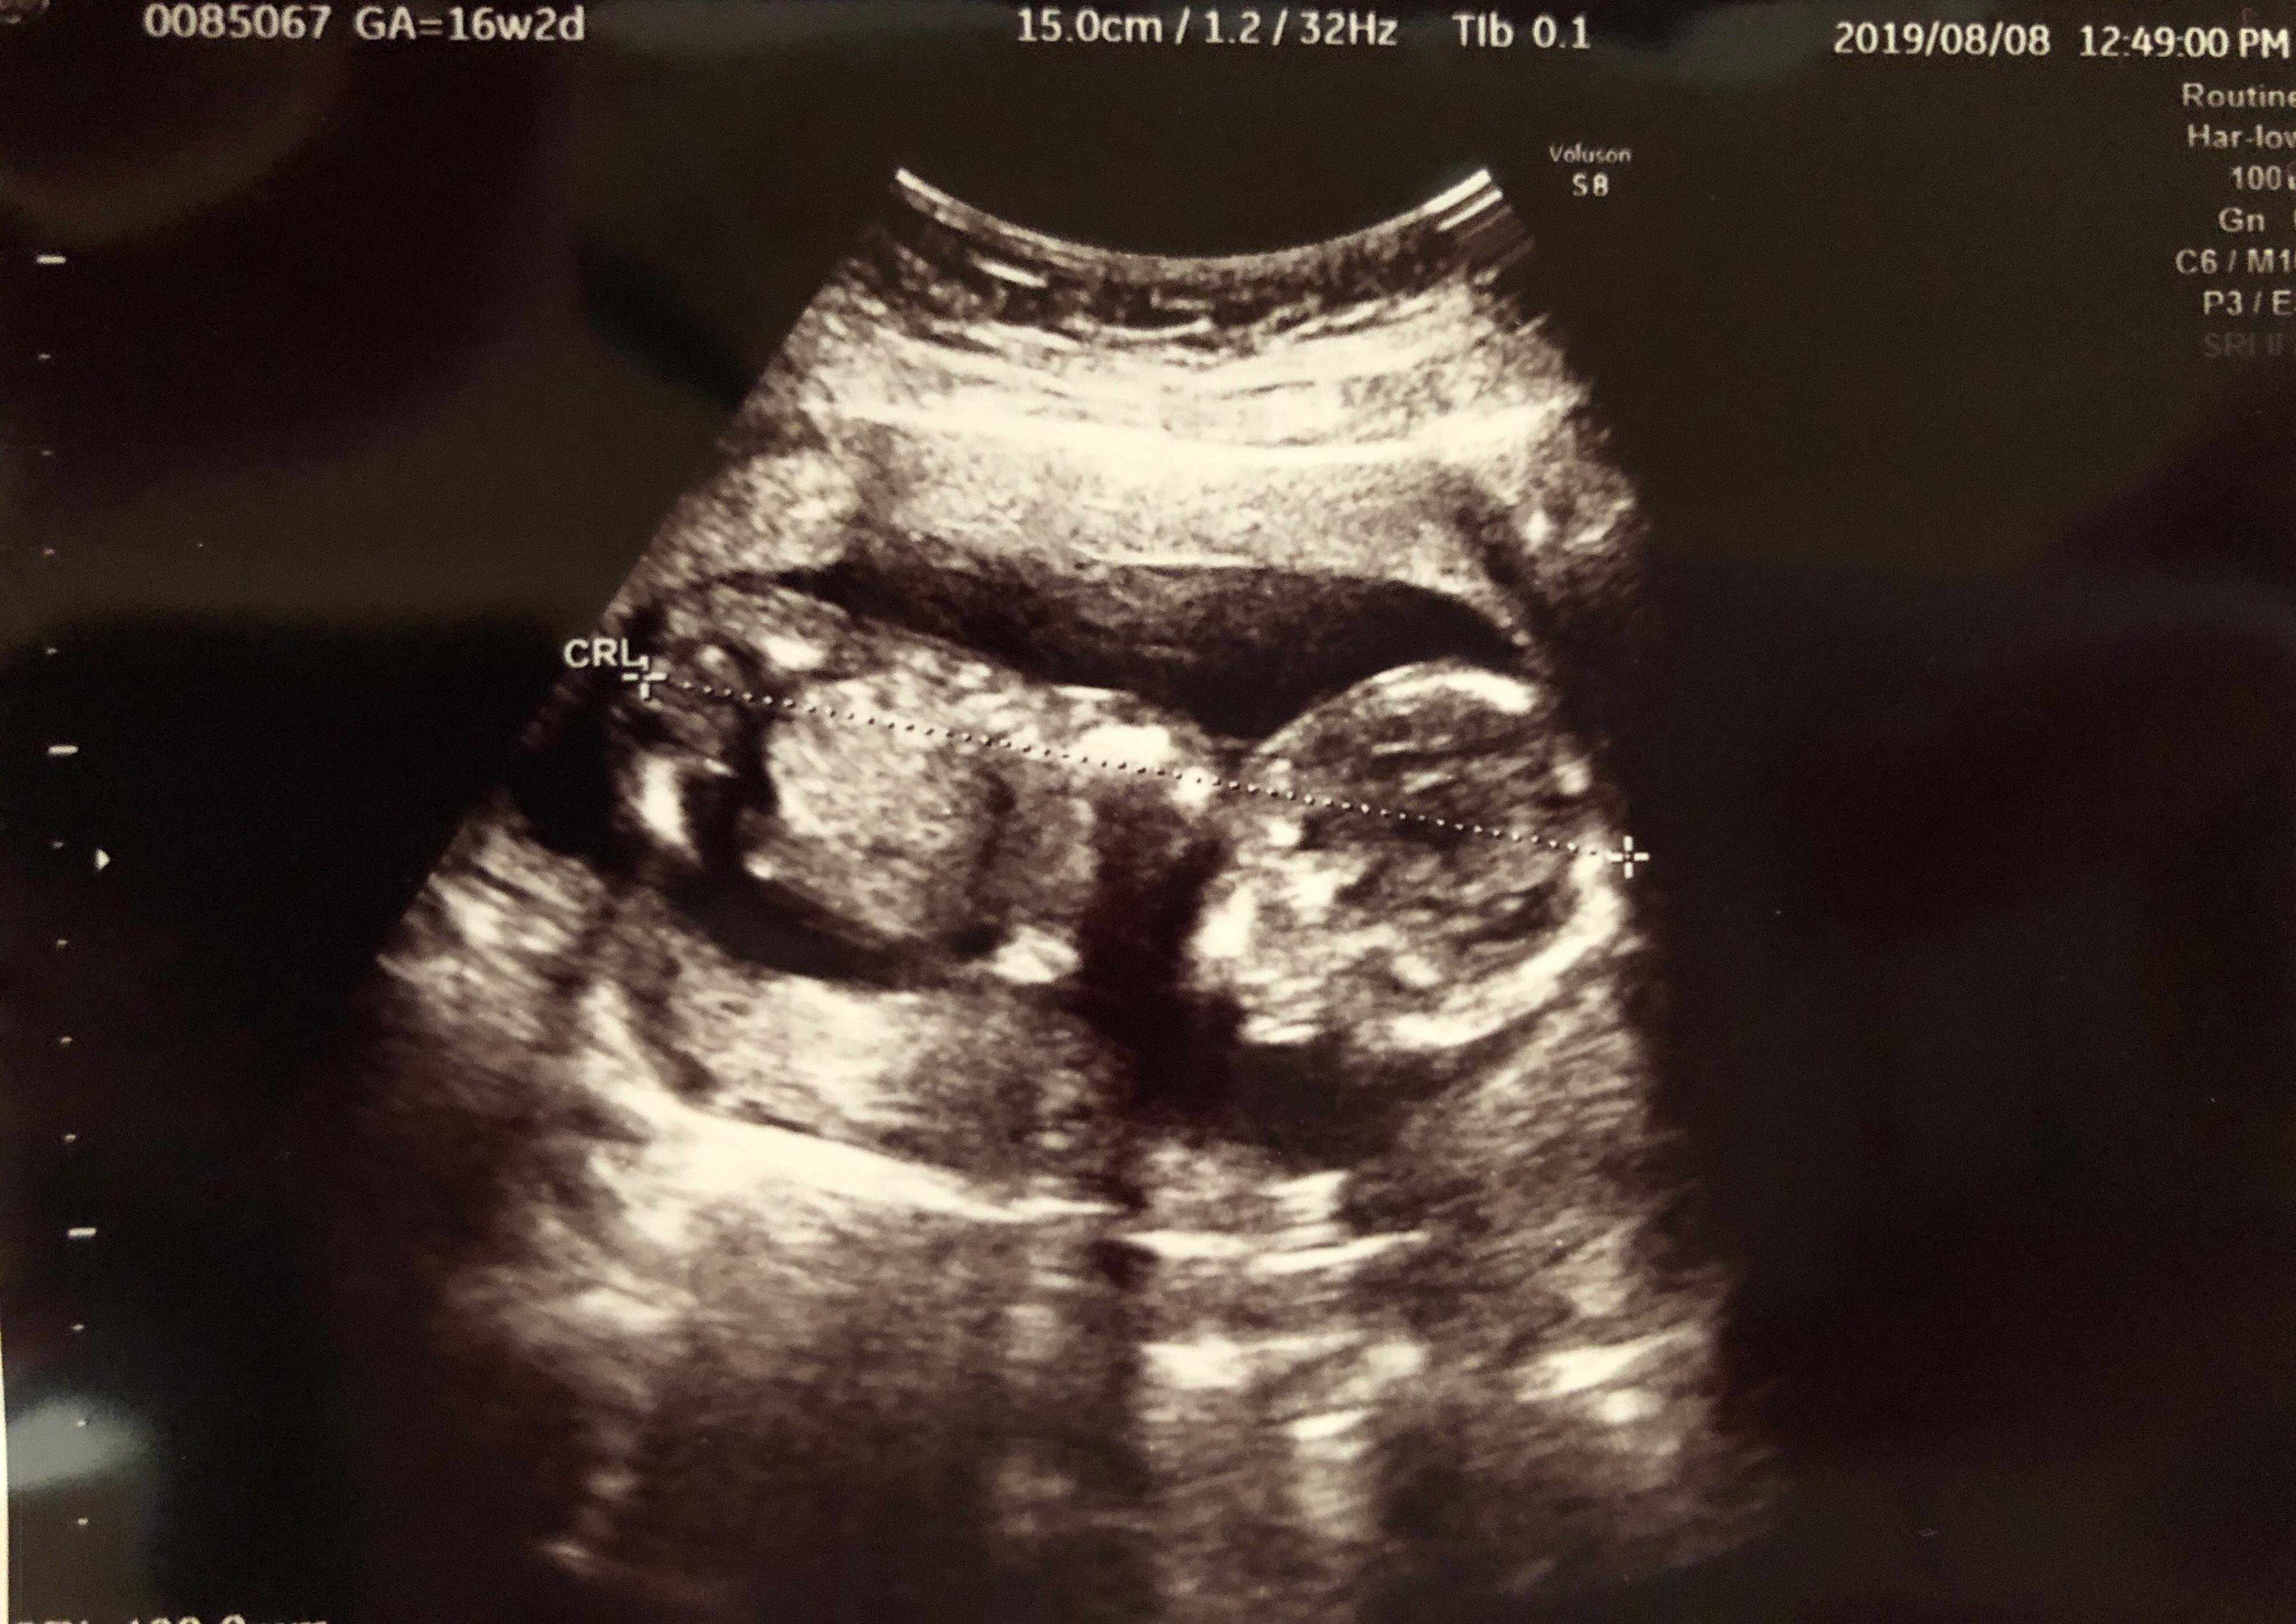

妊娠16週目 あっという間に安定期突入

妊娠16週のエコー写真で、安定期に入ったところです。次の健診までが長く感じていた長男のときとは違い、長男のお世話に追われて毎日が過ぎるので、私は「もう安定期!?」という感覚でした。

体調も赤ちゃんの成長も問題なく、この頃から「あれ? 動いた?」とわずかながらも胎動を感じるように。長男が寝てやっとゆっくりできる夜に、よく胎動を感じました。さらに、おなかも目立つようになりマタニティウェアやワンピースばかり着回していました。